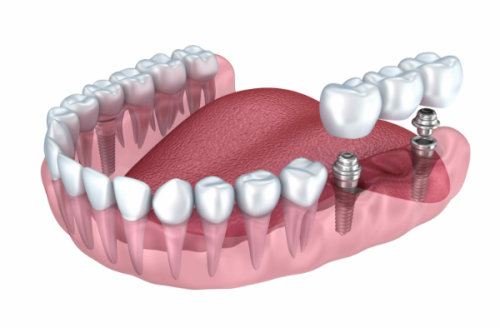

| 半口种植(韩系全固定) | 2.8万元起 |

| 全口种植(瑞士全固定) | 4万元起 |

| All-on-4 半口 | 5万元起 |

| All-on-6 全口 | 11万元起 |